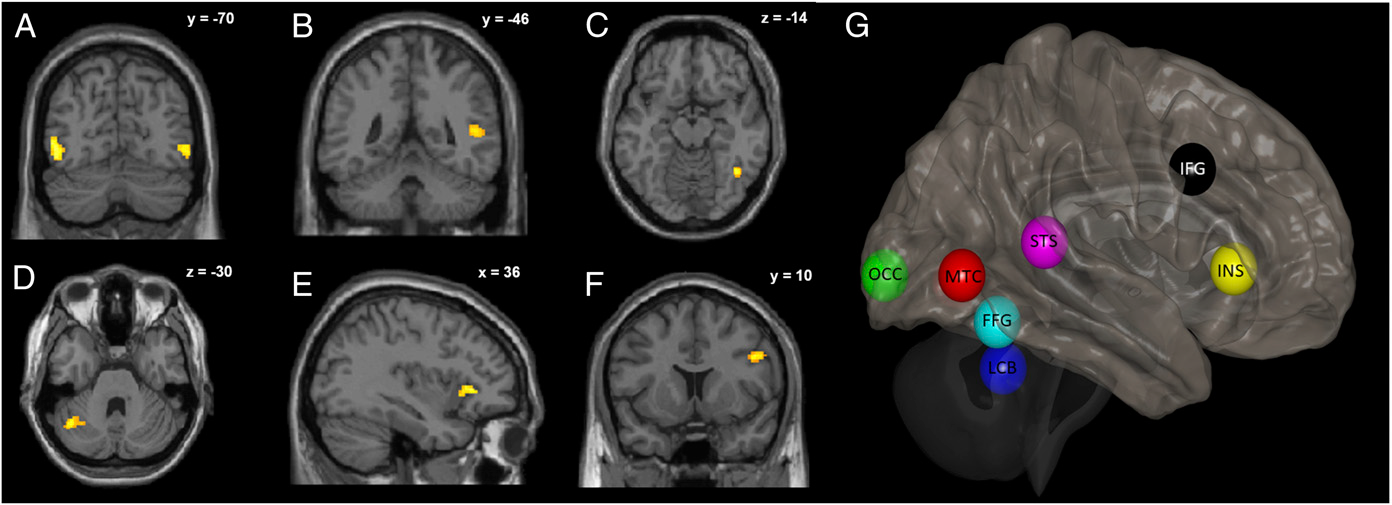

Neutrales und emotionales Punktlichtklopfen löst unterschiedliche Gehirnreaktionen aus. (A) Fünf Bilder veranschaulichen das Klopfen als eine Reihe von hellen Punkten auf einem dunklen Hintergrund. Die Punkte wurden auf dem Kopf, der rechten Schulter, dem Ellbogen, dem Handgelenk sowie dem ersten und vierten Mittelhandgelenk einer unsichtbaren, nach rechts gedrehten Person platziert. (B-D) Im Vergleich zu emotionalem Klopfen aktiviert neutrales Klopfen (B) die rechte Amygdala (x = 26; y = 4; z = -26, Koordinaten des Montreal Neurological Institute, MNI) und (C) die Mittellinie der Kleinhirn-Uvula (x = 0; y = -52; z = -46). (D) Die rechte Insula (x = 44; y = 4; z = -6) zeigt im Vergleich zu neutralen Klopfreizen eine höhere Aktivierung für emotionale Stimuli. Die Aktivierung wird auf die MNI T1-Vorlage überlagert. Die Schnittpositionen im MNI-Raum sind in der rechten oberen Ecke jedes Panels angegeben. Aus Sokolov et al. (2020). Proc Natl Acad Sci U S A. 117(34):20868-73.

Wie schließen wir auf das Fehlen von Emotionen in der Körpersprache? Im Gegensatz zur Erkennung emotionaler Signale ist die Frage, wie neutrale Körpersprache als solche erkannt wird, in den Neurowissenschaften noch kaum beantwortet. Allerdings ist sie von großer Relevanz für die Forschung im Bereich psychischer und neurologischer Erkrankungen, bei denen neutrale Signale als emotional fehlinterpretiert werden (wie etwa Autismus, Depression, Demenz oder Schizophrenie). Die funktionelle Kernspintomografie (fMRT) und das sog. Dynamische Kausale Modellieren (DCM) beleuchten den Zusammenhang neuronaler Kommunikation zwischen Amygdala und Insula mit unserer Fähigkeit, das Fehlen von Emotionen zu erkennen. Die Kommunikation zwischen der rechten Amygdala und der Inselregion kann nämlich vorhersagen, ob ein neutraler Ausdruck durch Körperbewegungen (hier Handklopfen) richtig erkannt wird. Bisher wurde angenommen, dass diese Bestandteile des limbischen Systems ausschließlich zur Wahrnehmung von Emotionen beitragen. Weiterführende Studien könnten neue Verfahren zur Diagnostik und Behandlung nach sich ziehen.